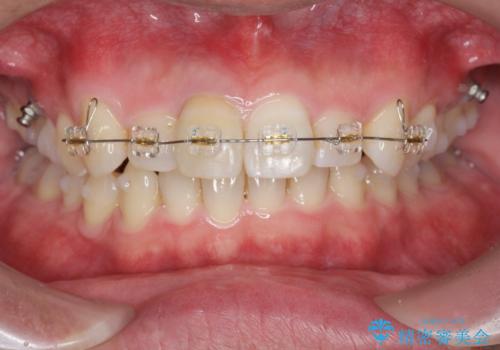

・深い噛み合わせ(ディープバイト) ・2級性の咬合関係(上顎前突)・前歯のがたつき

以上のような歯並びの問題をマウスピース矯正インビザライン・カリエール・マイクロインプラント・部分ワイヤー矯正

を用いて改善していきます。

深い噛み合わせと上顎前突の状態を治すのに時間がかかりましたが、治療後は理想的で安定した咬合関係となりました。